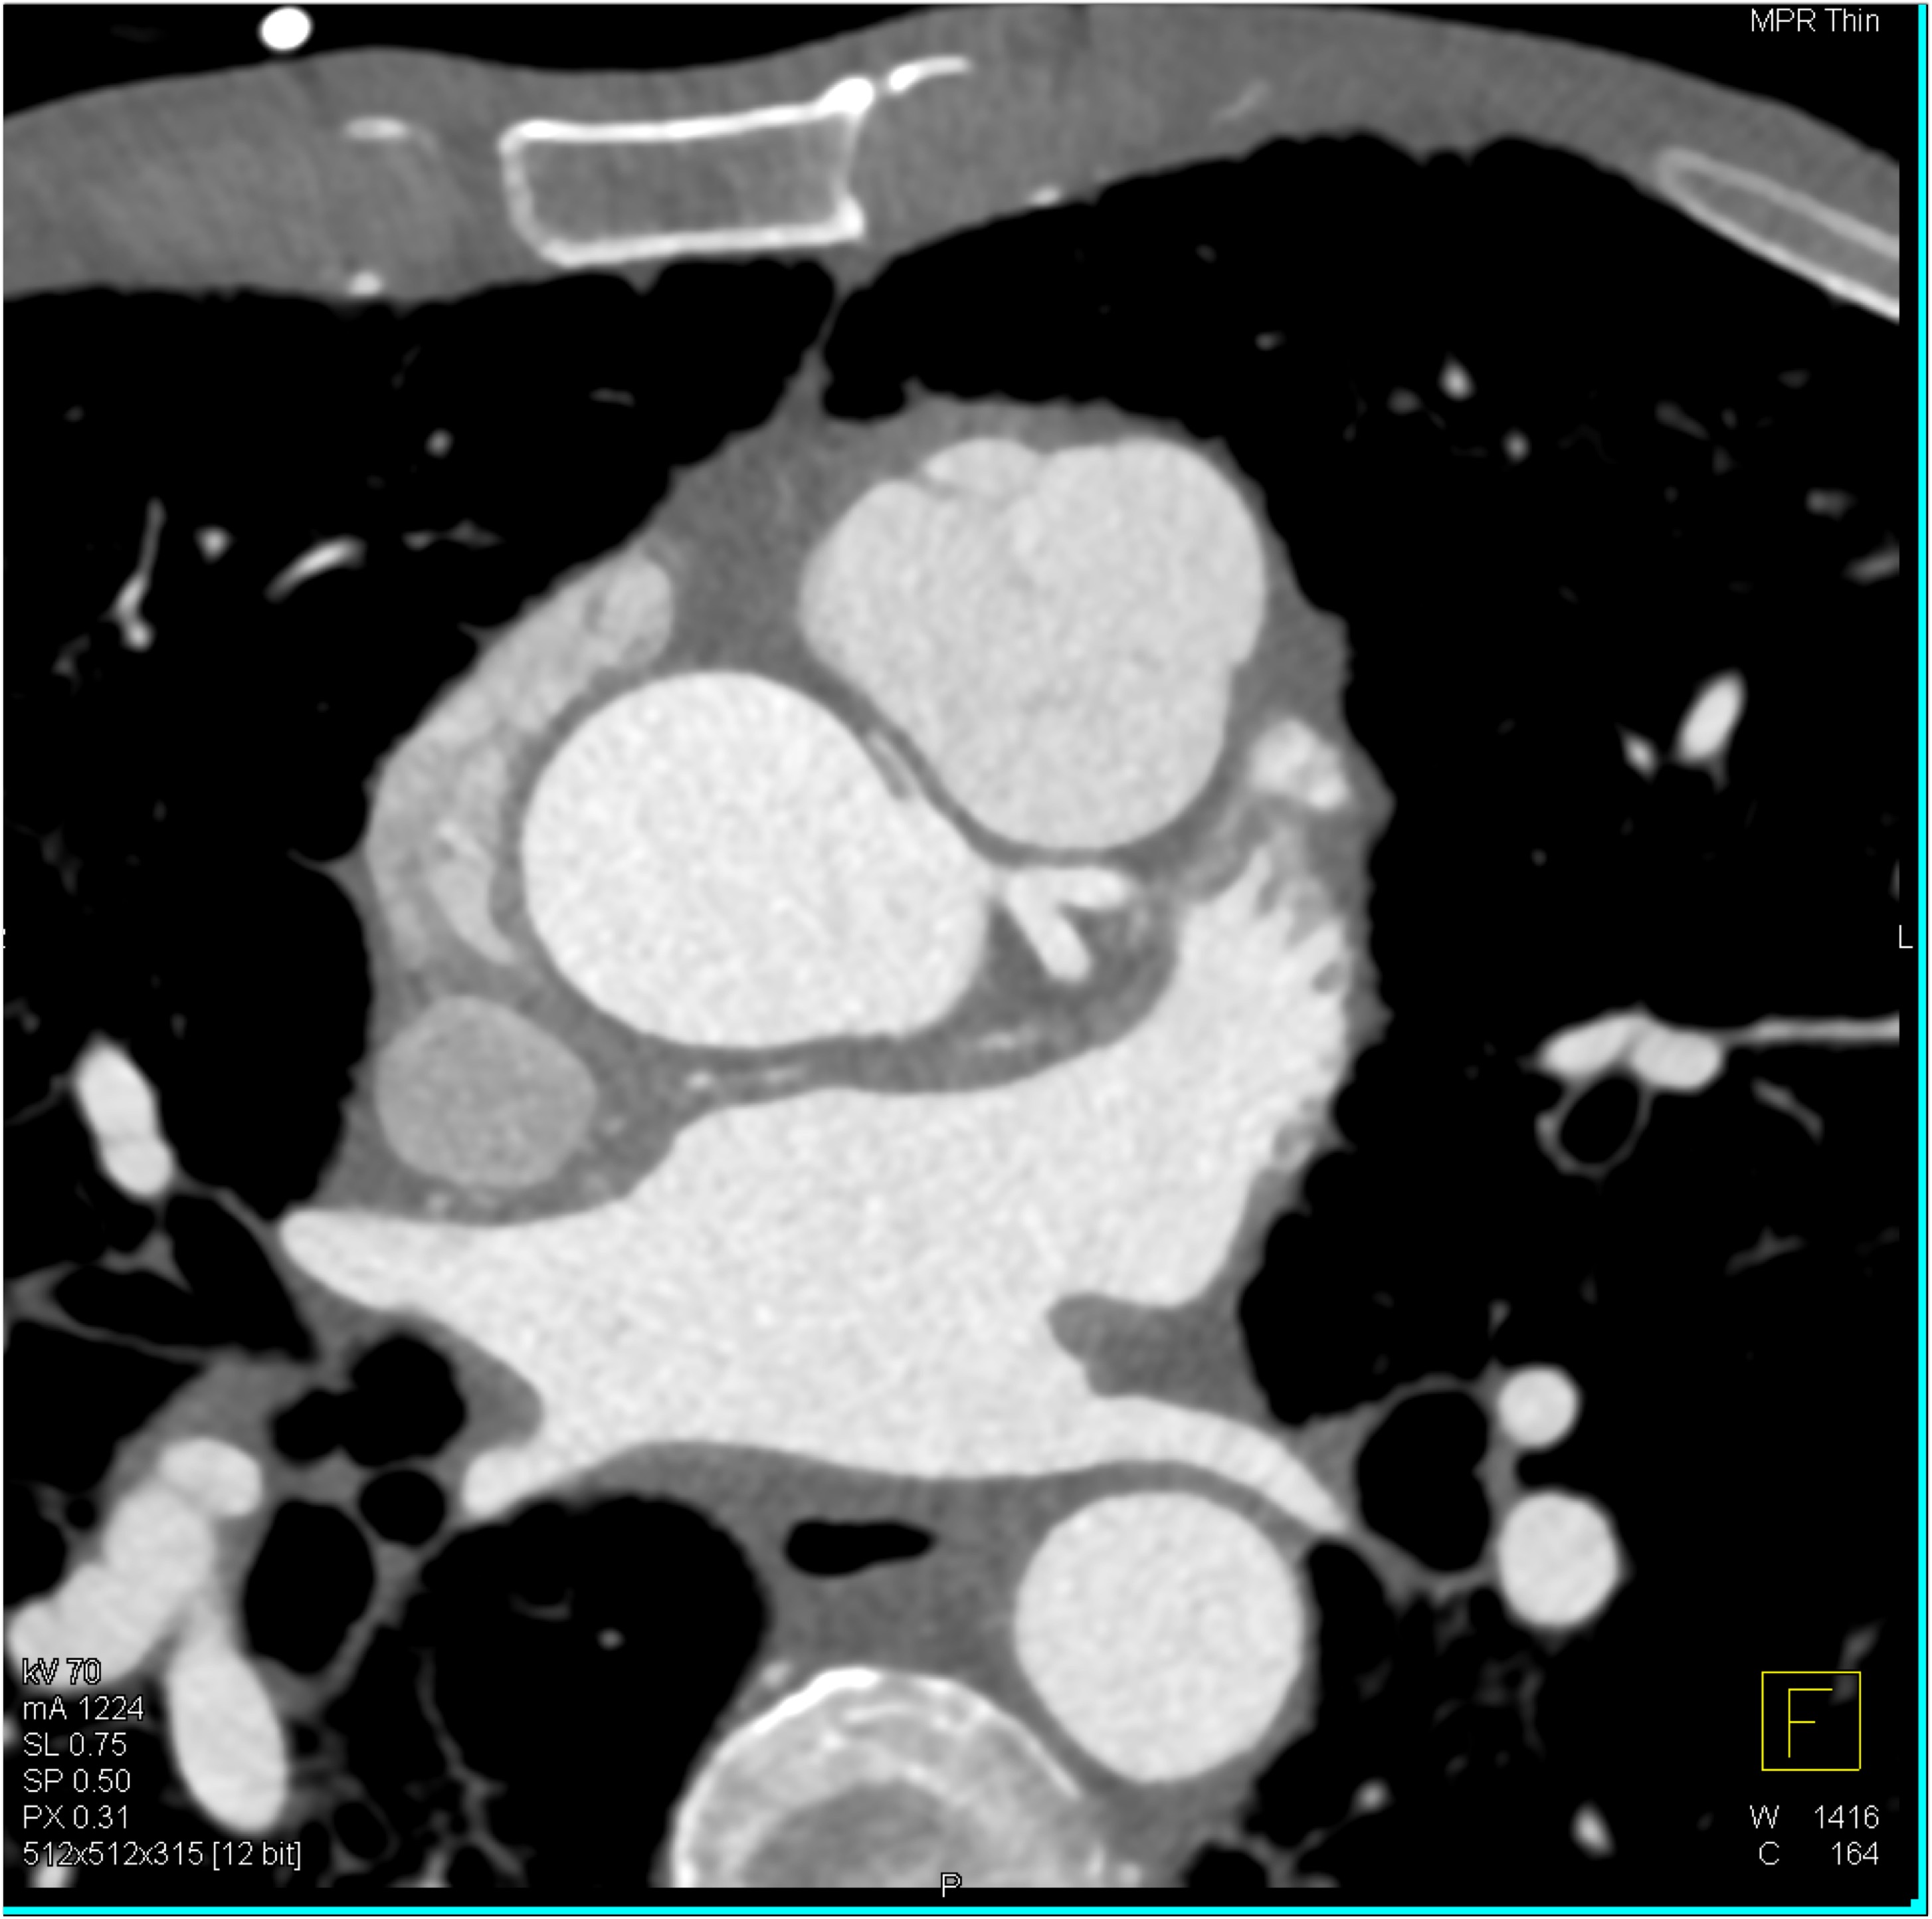

6) The most likely diagnosis in this case is?

vegetations in pulmonary valve

failed pulmonic valve

normal appearance of repaired pulmonary valve

abscess of the pulmonary artery